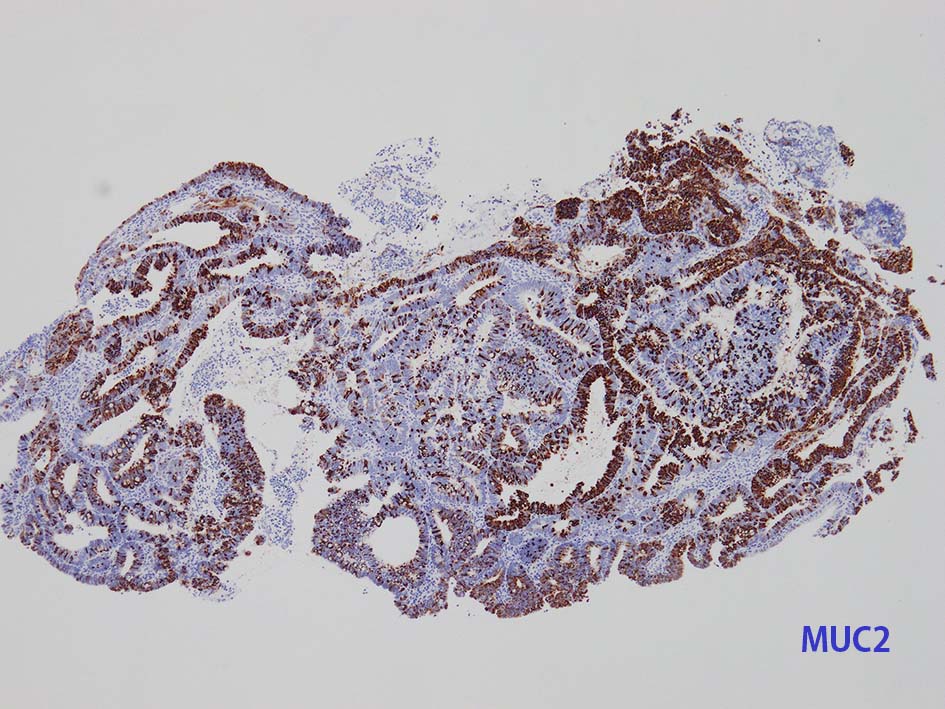

膀胱原発腺癌の診断に, サイトケラチン7および20、34βE12、トロンボモジュリン、CDX2およびβカテニンなどの免疫組織化学的パネルが提案されている。しかし他の原発部位に発生する腺癌と組織像だけでなく免疫組織化学的特徴が重複している. 原発性腺癌と転移性腺癌では予後や治療法が大きく異なるため, 鑑別診断において膀胱腺癌の診断を下す際には、臨床的、画像的、組織的、および免疫組織化学的な相関を注意深く確認する必要がある。

腸管型の腺癌。大腸の高分化腺癌と組織学的に区別は難しい.

mark-g.gif 免疫染色

GI tract, とくに大腸癌の膀胱浸潤/転移を最初に考えた.